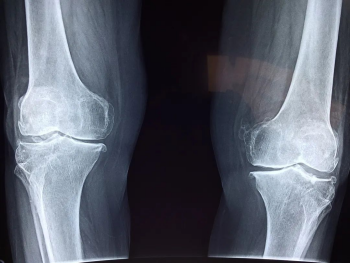

膝關節(jié)出現(xiàn)這些癥狀,可能已經(jīng)提示關節(jié)受損

如果你根本想不起來自己的膝關節(jié),首先表明它是健康的,當你開始關注你的膝關節(jié),可能就表明它出現(xiàn)了一些問題。

那么我們膝關節(jié)常出現(xiàn)的問題大概有兩類:

1.疼

這是最常見的情況,突然覺得膝蓋開始疼了,疼痛有由輕到重的區(qū)別,再一個就是它的部位,如果用手掌去摸到自己左側的膝蓋的話,用手掌心去扣住膝蓋上面的髕骨,扣住它之后,當大拇指自然下垂的時候,能夠碰到一個間隙,這個是膝關節(jié)內(nèi)側的間隙,如果這個位置疼痛,要小心半月板或者骨關節(jié)炎的一些問題,如果這個位置更靠上方或者更靠膝關節(jié)的下方,那有可能是來自于韌帶,這是我們根據(jù)疼痛的部位來判斷的。

2.響聲

有的時候膝關節(jié)會出現(xiàn)一些響聲,很清脆的一次彈響,不伴有疼痛的,可能是一些生理性的彈響,比如說我們滑膜增生等。如果退行性的骨關節(jié)病、關節(jié)炎,它的響聲是非常有特征性的,就像冬天你去握一把雪,雪球就發(fā)出咯吱咯吱的聲音,這種握雪感是非常典型的骨關節(jié)炎的一個表現(xiàn),叫作骨摩擦音。